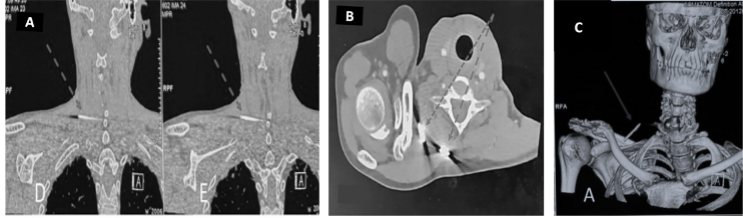

Clinical examination revealed no signs of radiculopathy, motor weakness, or restriction in neck mobility. However, a palpable small swelling (3 × 2 cm) was noted in the right supraclavicular region. The carotid artery was well palpated, and the swelling was lateral to the vascular bundle. Radiographs of the shoulder and neck revealed two broken K-wire fragments – one located in the right supraclavicular region and another posteriorly near the cervical spine (Fig. 1b and c). The shoulder radiograph showed a malunited lateral end clavicle fracture fixed with tension band wiring over two K-wires, both of which were broken distally. A non-contrast computed tomography (CT) scan of the neck was performed to delineate the exact position of the migrated wires (Fig. 2). The case was reviewed in a multidisciplinary team setting with input from an otorhinolaryngology expert. Routine pre-operative laboratory investigations were within normal limits, and the patient was planned for elective hardware removal.

Figure 2: Coronal computed tomography (CT) sections localizing the exact position of the migrated wires (a); Axial CT image (b), and 3D-reconstructed images from CT scan showing the position of the migrated K-wires (c).